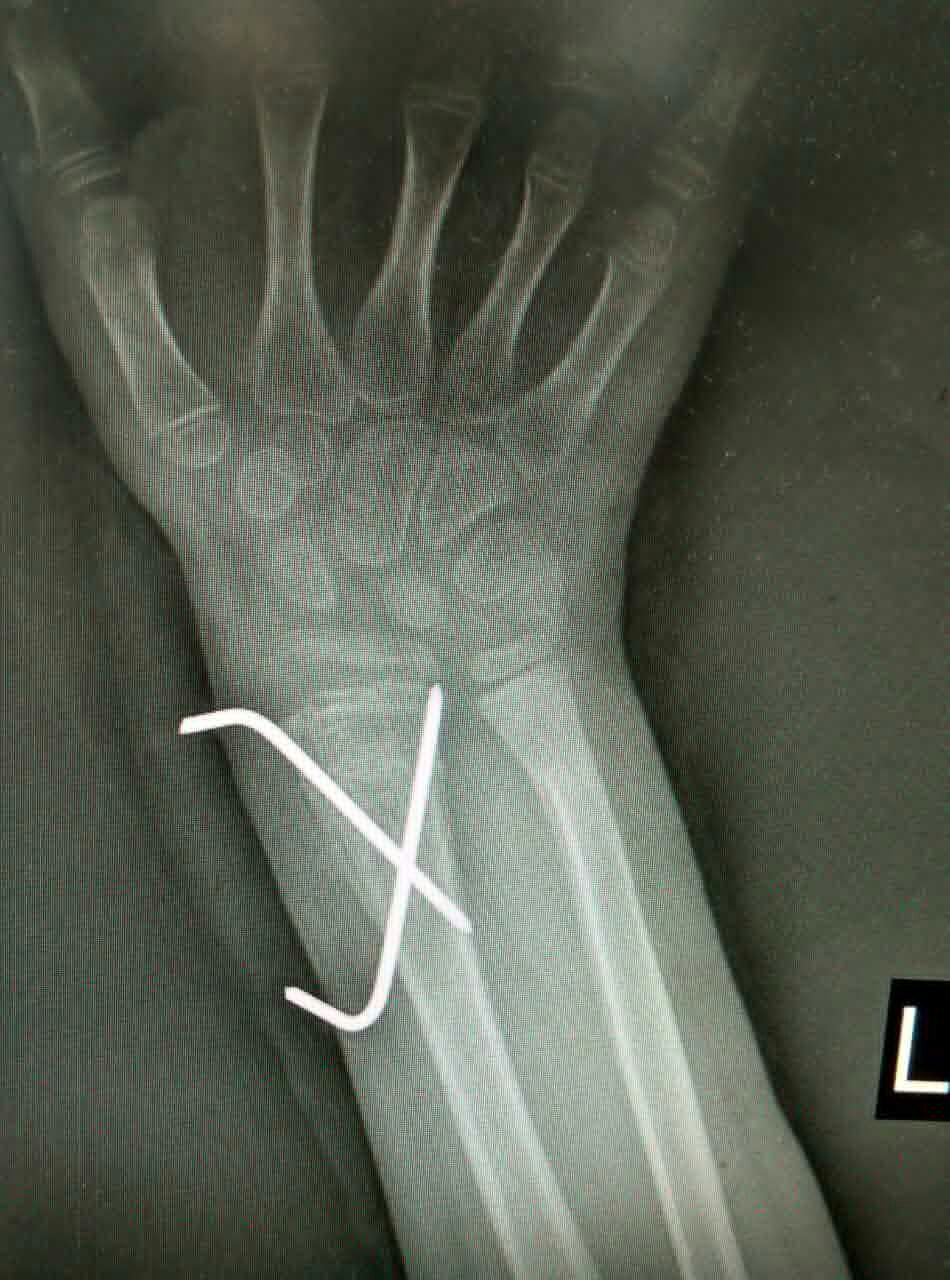

患儿,男,10岁,因左桡骨远端骨折畸形愈合5周来我院就诊。患儿家长曾在我市多家医院就诊,均认为切开复位,传统手术切口6-8cm。腕部血管、神经较多,共约20余条,稍有不慎,将给患儿造成较大后遗症,瘢痕永久存留,外观不美,且费用昂贵。我科谢瑞卿主任看过病人后决定采取微创闭合复位内固定,起初家属半信半疑,但后来经过耐心解释后决定在我院手术治疗。于2016-01-25在全麻下行左桡骨远端陈旧性骨折闭合复位内固定术,微创切口0.5cm左右,我们成功避免了各种意外事件的发生,截骨复位,我们巧妙应用骨刀在微创手术中的优点,成功闭合复位,术后复查拍片骨折复位满意。在骨科全体医护人员的积极治疗护理下,于春节前临床治愈出院。术后6周复查骨折已骨性愈合,腕关节功能良好。患儿家长万分感谢,赞叹西安凤城医院有如此精湛的技术和优质的服务质量与态度。

术后X光片